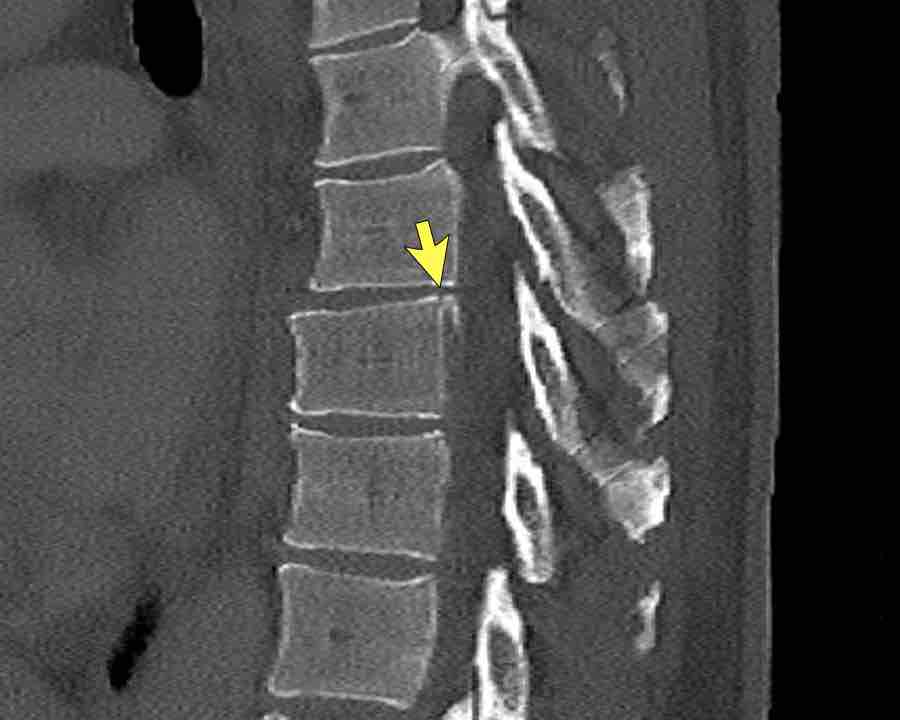

Findings

- The most severe level is L4/5 with dislocation (dotted lines)

- Facet fractures at L4 (arrows).

- A4 burst fracture (circle).

Conclusion:

Injury type C + A4 at L4/5.